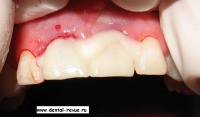

24. Временные коронки после установки.

25. Временные коронки после установки.

26. Временные коронки сразу после установки при сомкнутых зубах.